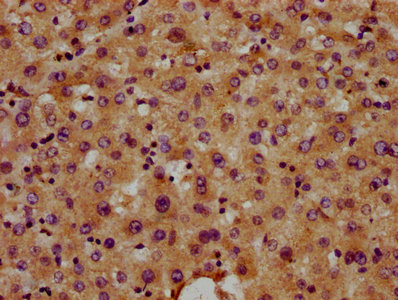

IHC image of CSB-PA840582LA01HU diluted at 1:400 and staining in paraffin-embedded human liver tissue performed on a Leica BondTM system. After dewaxing and hydration, antigen retrieval was mediated by high pressure in a citrate buffer (pH 6.0). Section was blocked with 10% normal goat serum 30min at RT. Then primary antibody (1% BSA) was incubated at 4°C overnight. The primary is detected by a biotinylated secondary antibody and visualized using an HRP conjugated SP system.

Application Recommended Dilution IHC 1:200-1:500 -